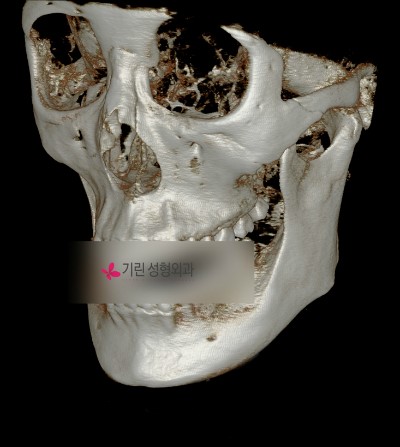

귀밑각은 크지 않지만 턱이 길어서 길이줄임수술과 긴곡선절골술이 병행된 경우.

![턱의 길이를 줄여주는 턱끝수술[앞턱길이줄임술] 관련 이미지 1](https://pub-9f2bb3498faf4d1d8714b41df24753e3.r2.dev/content/clinics/archive/pr7y376obf/naver_blog/girinlife/assets/by_hash/cefbc7a2bea84c7995e9682253b74be3d44e7543a0fcf621aa4d47e049227a4d.jpg)

수술 후 앞턱에 보이는 고정장치(의료용 플레이트)